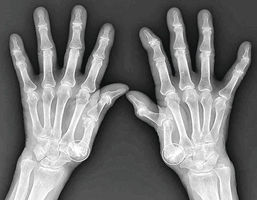

心身健康 ドクターに聞く 母指CM関節症 整形外科医 今泉佳宣さん 2026年2月26日 05:00 母指CM関節症のエックス線写真(丸で囲んだ箇所) ◆親指付け根の関節に痛み 母指(... 残り1049文字(全文:1063文字) この記事をお読みいただくには「デジタルプラン」または「宅配+デジタルプラン」の会員登録が必要です。無料会員の方はログインしてマイページからコース変更してください。デジタルプランまたは宅配+デジタルプランをご登録中の方はログインしてください。 岐阜新聞デジタル会員に登録すると 無料会員向け記事が読める ニュースレターで最新情報が受け取れる デジタルプラン、宅配+デジタルプランなら Webオリジナルコンテンツが読める 紙面ビューアが読める チケットの先行発売に参加できる お得なクーポンが使える 新規登録ページ ログインページ トップ 岐阜のニュース 心身健康 ドクターに聞く 母指CM関節症 整形外科医 今泉佳宣さん 関連記事 ぎふサテ! 午後4時59分~ 前橋で豚熱確認 2000頭殺処分開始 窃盗被害2億円超 安八民泊拠点グループ、捜査終結 14都府県、自動車盗や侵入盗 合同捜査本部 群馬3人死亡 被告側が控訴 危険運転認定に不服 発毛に貢献 第3の細胞発見 理研などマウス実験 体外で再現成功 自動車盗4年連続増 25年6386件、ランクル最多 警察庁 おすすめ記事 岐阜県、26施設の料金を値上げへ 物価高騰や人件費上昇に対応 選手勧誘に苦戦 ライバルは岐阜総合、岐阜三田 秋田和哉さん 【ぎふ高校野球 名将流儀】 FC岐阜、開幕4連勝狙う 28日に敵地でJ2札幌戦【百年構想リーグ】 スキークロス新井選手「好きなことを納得するまで」 高山市の母校で語る【ミラノ冬季五輪】